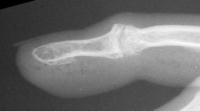

Final implant radiographs.

The trial implant sizer shows the true size of the implant. The final implant has a radiolucent coating  which makes it appear smaller than it is on Xray.